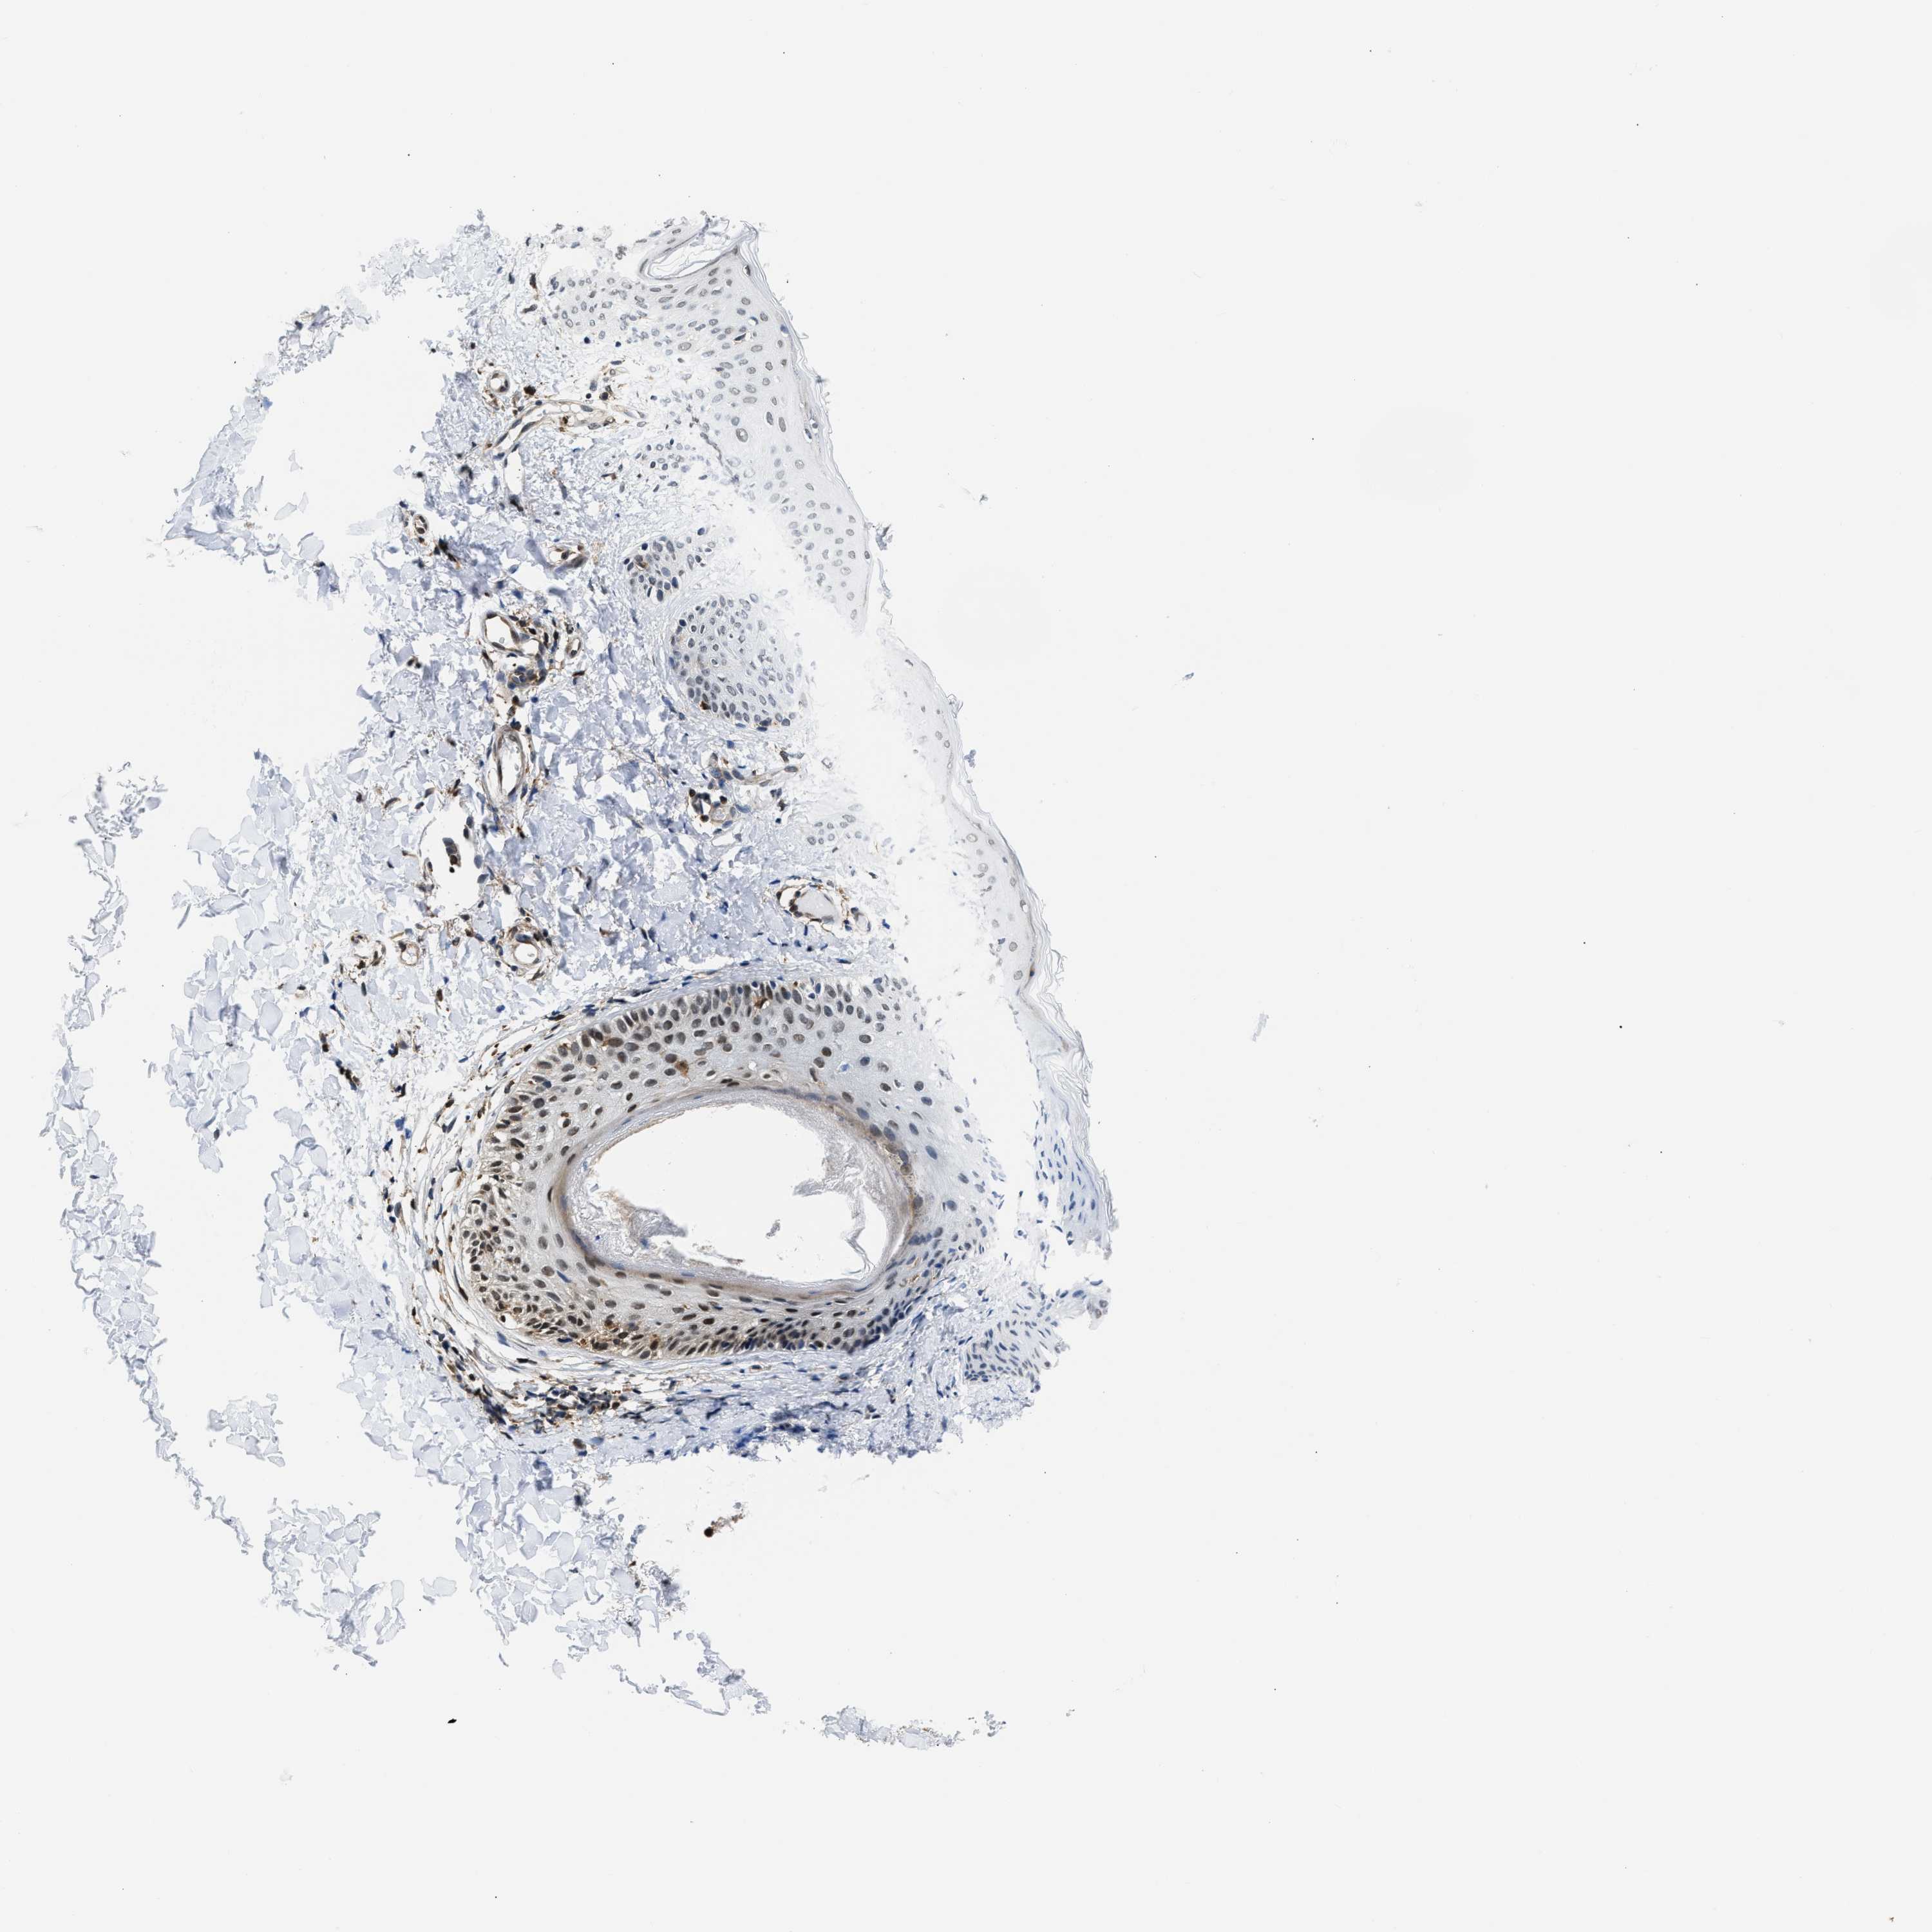

SKIN 2 - Antibody stainingi

Antibody staining in the annotated cell types in the current human tissue is reported as not detected, low, medium, or high, based on conventional immunohistochemistry profiling in selected tissues. This score is based on the combination of the staining intensity and fraction of stained cells. Each image is clickable and will lead to virtual microscopy that enables deeper exploration of all samples and also displays staining intensity scores, fraction scores and subcellular localization as well as patient and tissue information for each sample.

Antibody HPA015083

Epidermal cells Not detected